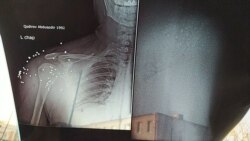

– Я два дня находилась в больнице. Врачи не оказали парням никакой помощи, не извлекли пули из их тел. Когда я спросила врачей, почему они не оказывают им никакой помощи, они заявили нам, что им поступил такой приказ «сверху». В больницу приехал судмедэксперт, он пощупал живот моему внуку и уехал. Мы сделали рентген. Выяснилось, что в теле моего внука имеется 37 пуль. Пули лежали в области плеча и живота, еще семь пуль остались в области селезенки. Врачи не извлекли из его тела ни одной пули. Я была в шоке, когда врач заявил, что пули сами выйдут из тела. Мой внук температурил, когда его увозили милиционеры. Но, несмотря на это, конвой посадил его в машину и увез в изолятор. Разве можно раненного человека помещать в следственный изолятор, тем более, если он является потерпевшим?, – возмущается в разговоре с нашим журналистом бабушка одного из пострадавших.

Рентгеновский снимок, сделанный Шохаббосу Джаббарову.